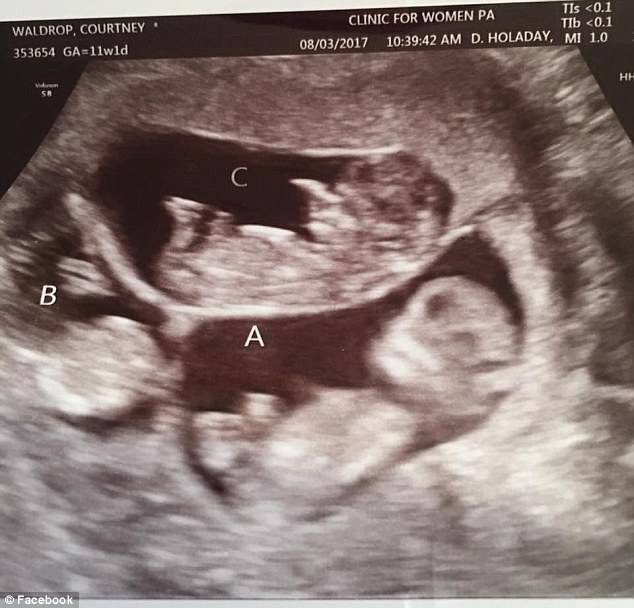

Courtney ed Eric Waldrop sono una coppia americana che, prima di realizzare il loro sogno di avere bambini ha dovuto affrontare diversi aborti. Il loro primogenito Saylor è nato nel 2008, poi però la coppia ha dovuto ricorrere alla fecondazione in vitro per avere altri figli. I loro due gemelli Wale e Bridge ora hanno 5 anni.

Dopo un ultimo aborto spontaneo il medico della coppia ha messo Courtney a basso trattamento di fertilità per impedire che la donna avesse una gravidanza plurigemellare. Durante un controllo però i tecnici hanno sentito 6 battiti nell’utero materno. Una gravidanza di 6 bambini era ad alto rischio, i bambini infatti potevano nascere pre-termine. Anche per la mamma inoltre ci sono dei rischi:

Allo stesso tempo i parti multipli per la fecondazione in vitro sono scesi dal 48% al 32%. Courtney ha tenuto aggiornati famigliari e amici con una pagina su Facebook, a 11 settimane ha scritto: “pregate che il mio appetito mi permetta di mangiare come non ho mai fatto prima”. Sembrava impossibile portare completamente a termine una gravidanza di 6 bambini e la mamma infatti sperava di arrivare almeno a 30 settimane.